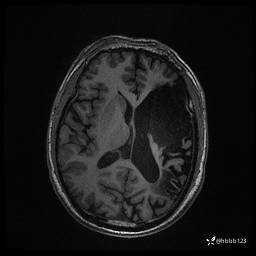

患者男,43岁。

简要病史:癫痫患者复诊,昨日发作5-6次,建议住院进一步治疗。

入院完善脑癫痫组合序列:

CUBE FLAIR横断位: